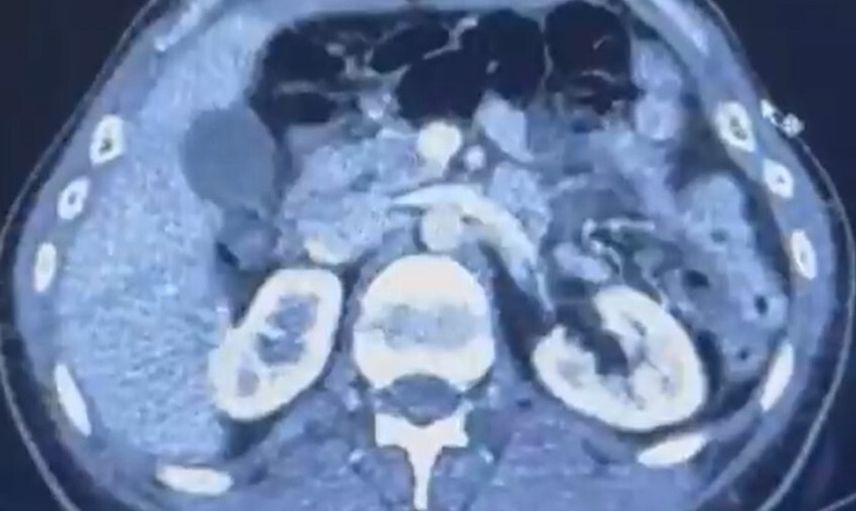

Kayseri Şehir Hastanesi'nde yapılan iç beden muayenelerinde, şüphelilerin mide kısmında 50 adet kapsül halinde toplam 554 gram uyuşturucu madde bulunduğu tespit edildi.

ŞÜPHELİLERİN MİDESİNDE KAPSÜL ŞEKLİNDE YARIM KİLO UYUŞTURUCU MADDE ELE GEÇİRİLDİ.